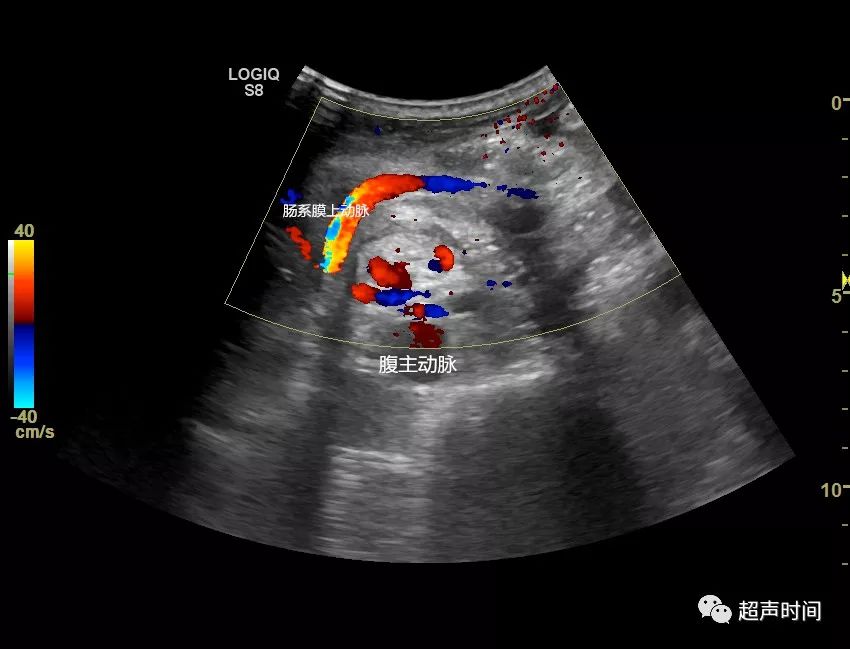

图 6 和图 7 二维和 cdfi 显示肠系膜上动脉和伴行的肠系膜上静脉发生

上图:彩超检查,可以显示肠系膜上动脉和肠系膜上静脉呈扭转状的位置